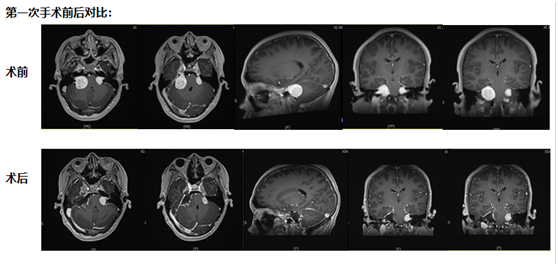

第一次手术:从耳后开口,既要拆瘤又要保听力

考虑到小倪才21岁,团队没选 “一刀切” 的方案,而是决定从耳后开一个约10厘米的小口 —— 这个位置能精准摸到耳朵旁边的肿瘤,还能尽量避开控制听力、面部活动的神经。

手术当天,医生在显微镜下一点点 “剥” 肿瘤:剥到肿瘤深处时,医生发现再往里切,必然会伤着听力神经。“停!这里留一点点,先保听力。” 团队果断调整,把能安全切除的肿瘤全清干净,再仔细止血,避免术后出血。